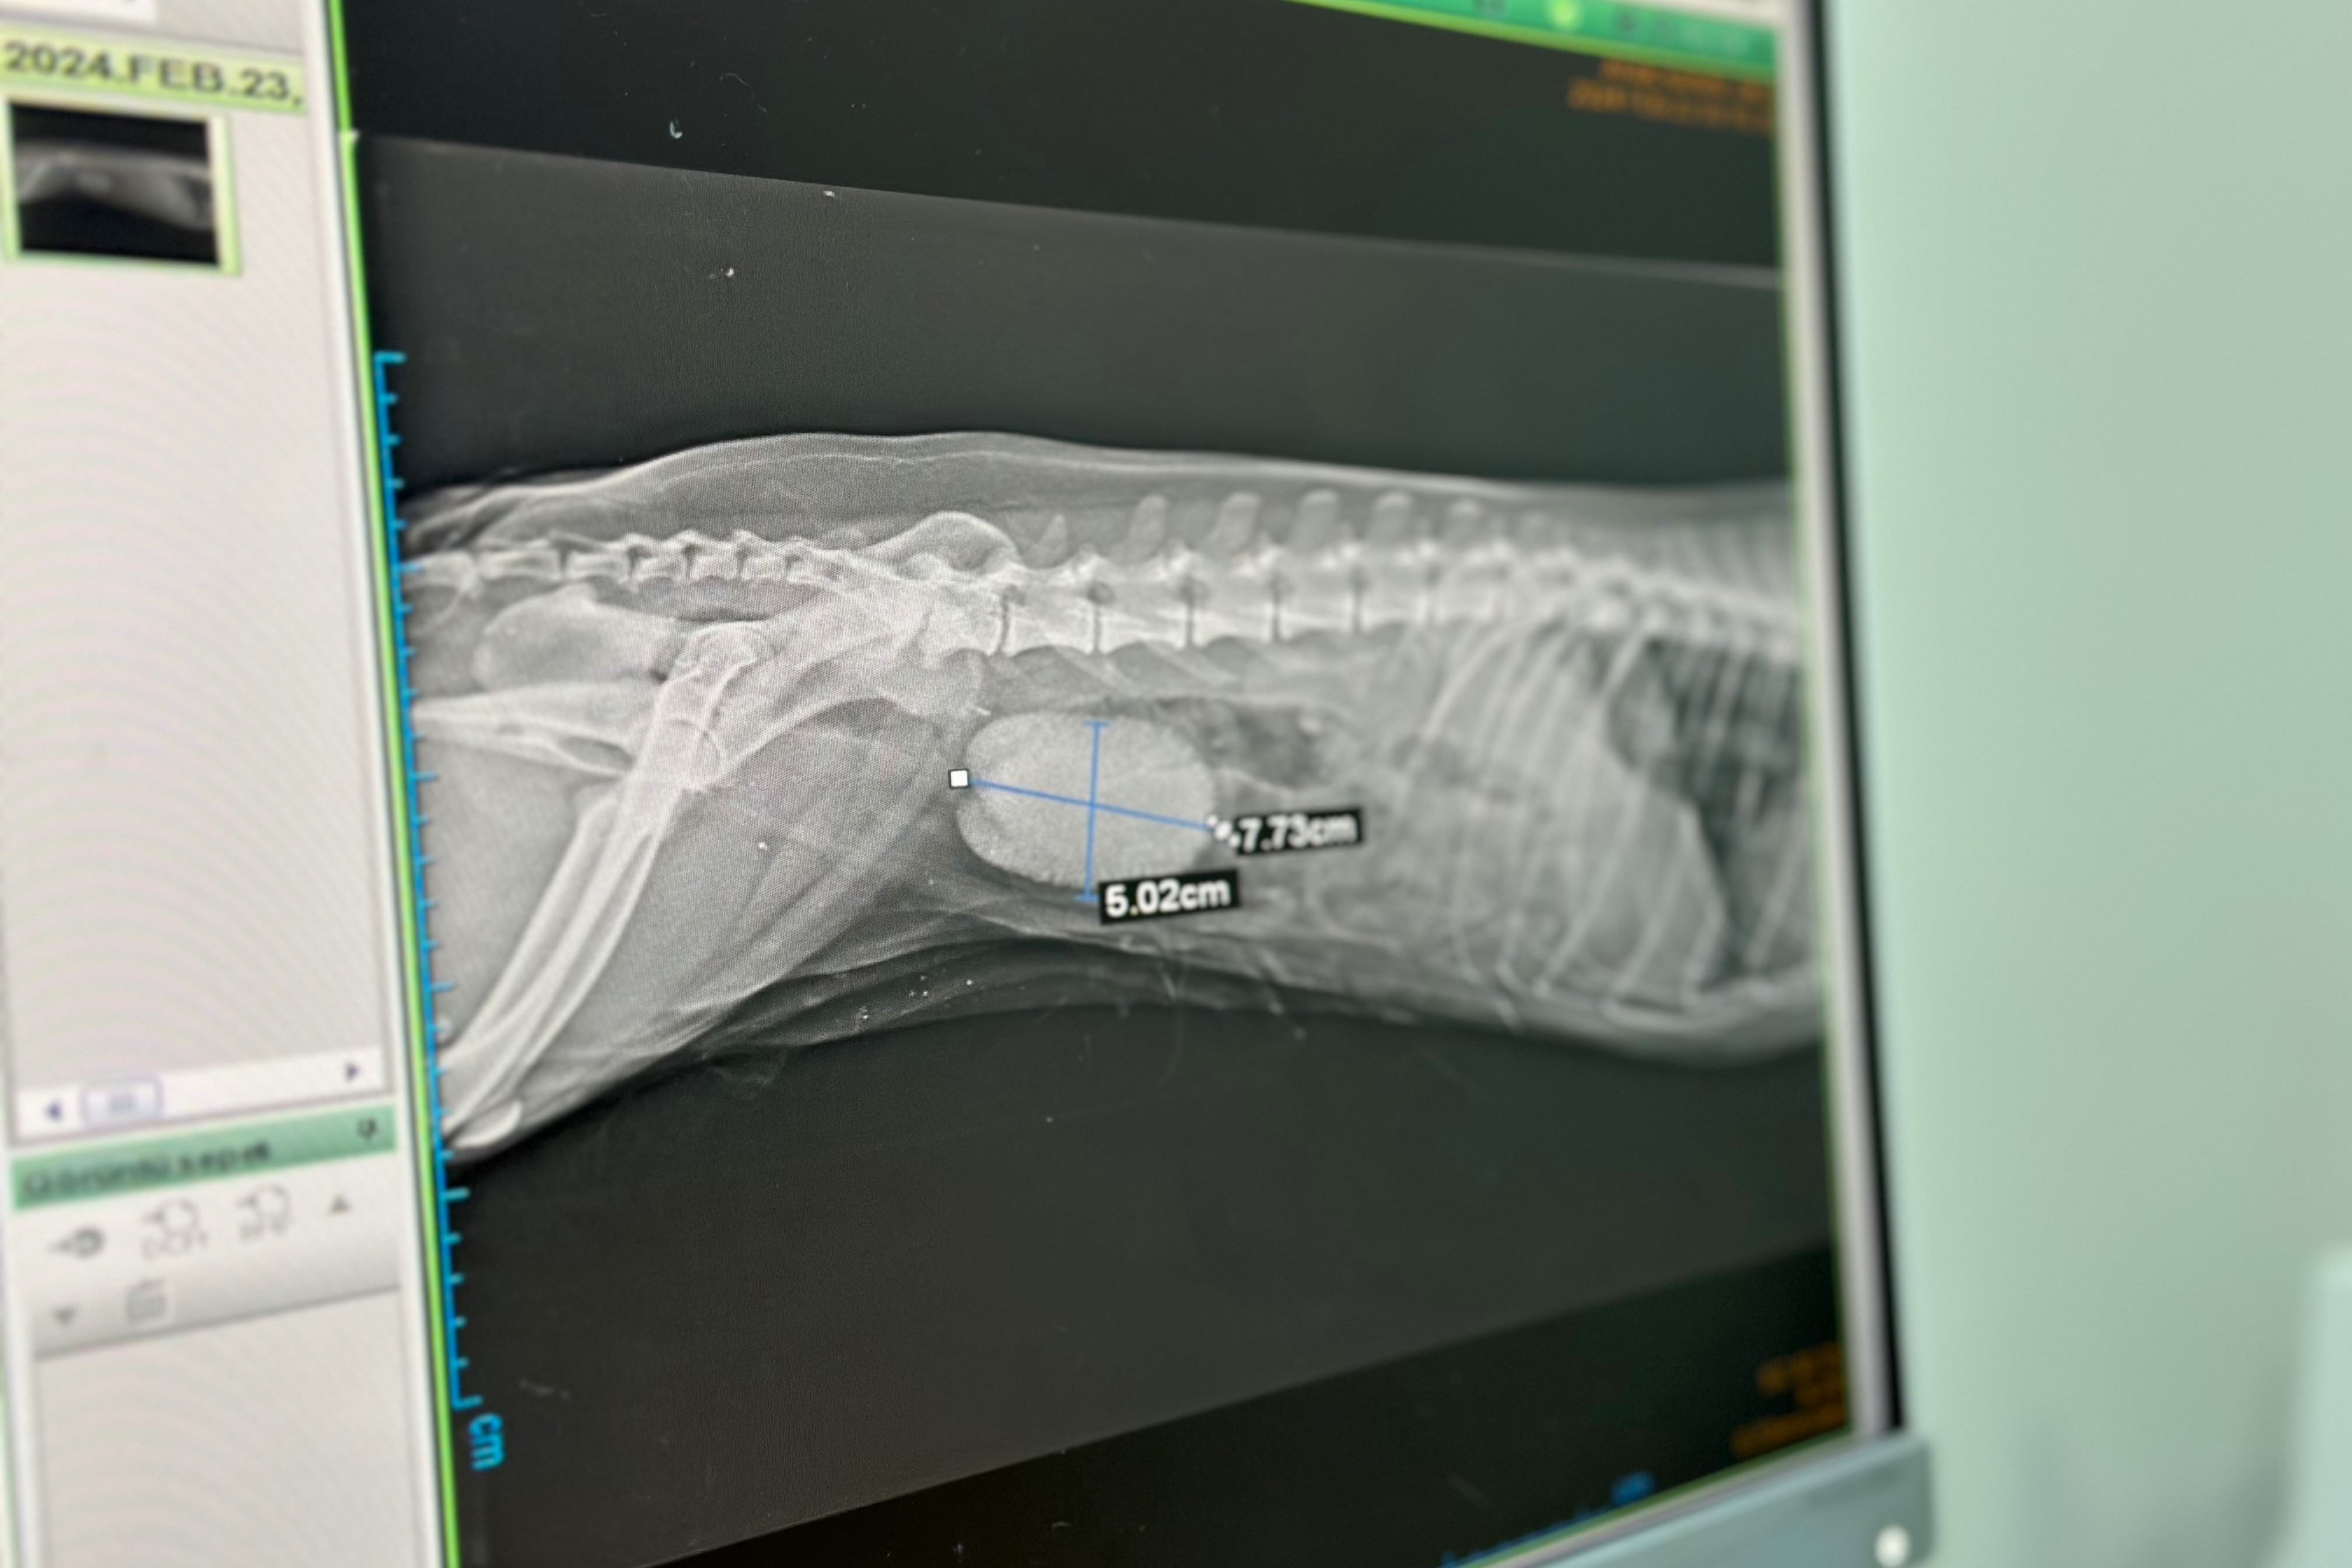

Taşın neredeyse kesenin tamamını doldurduğunu belirten Prof. Dr. Yayla, “Ameliyat için hastanemize gelen fındık isimli köpeğin idrar kesesinde taşı vardı. İdrar kesesinde taş olduğu bulgularıyla zaman zaman karşılaşıyoruz ama bu boyutta taş nadir karşılaşılan bir durum. Yaklaşık 8 ve 5 santimetre ebatlarında bir taşı vardı. Hayvanın kendisi de yaklaşık 10 kilogram. Neredeyse kesenin tamamını bu taş doldurmuştu” dedi.

Fındık’ın sağlık durumunun iyi olduğunu dile getiren Yayla, “Fındık isimli köpeğin şikayeti sancılı ve kanamalı idrardı. O yüzden ameliyat önerdik. Tedavisi de ancak ameliyatla mümkündü.

Ameliyatımız çok güzel geçti. Taşı da çıkardık. Şu an hayvanın durumu iyi. Taburcu işlemlerini başlatacağız. Fındık, 10 yaşında bir köpekti.

Hasta sahibi 3 yıl önce taşı fark etmiş. Ama anesteziden kaynaklı geciktirmiş. Dolayısıyla taş keseyi tamamen dolduracak kadar büyümüştü” ifadelerine yer verdi.